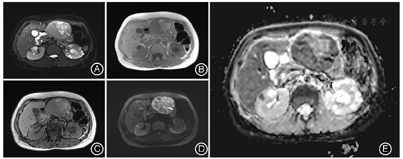

患者入院后查肝胆胰脾彩超提示:左肝混合回声团,肝癌待排。实验室检查提示:乳酸脱氢酶785 IU/L,乙肝核心抗体定量6.16S/CO,肿瘤指标无殊。查体:腹平软,剑突下轻微压痛、反跳痛。胸骨柄处肿胀明显,压痛阳性。MRI增强检查提示:肝左外叶占位,恶性肿瘤(肝细胞癌可能大)伴出血考虑(图1,图2)。为明确肿瘤转移情况,患者完善18F-FDG PET-CT检查提示:1.左肝外叶软组织肿块伴FDG代谢环形增高,首先考虑肝脏恶性病变;2.胸骨结核术后,胸骨柄右前方软组织结节伴钙化,首先考虑结核浸润(图3)。

由于HEAML内缺乏或极少含脂肪组织,MRI T1WI及同反相位上病灶内脂肪不易发现,当其增强表现与肝细胞癌(Hepatocellular carcinoma,HCC)重叠时,两者的鉴别尤为困难。本例HEAML病灶实质在反相位上未见信号减低,增强后延迟期信号低于周围肝实质,且可见环形强化的假包膜,因而容易在MRI影像表现上想到HCC的诊断。

有研究显示,HEAML富含迂曲扩张的厚壁血管,即增强后病灶内点条状血管影对两者的鉴别诊断有重要意义[8,9]。HCC的肿瘤血管主要为肝动脉,轮廓不光滑,血管不成熟、不连续,欠规则,走行僵直,门静脉期不显示,而HEAML中心血管为畸形静脉,表现为迂曲、流畅、光滑、粗细不等的强化血管,即肿瘤内"中心强化血管征",为HEAML特征性表现。因HEAML的肿瘤血管类型及含量不同,肿瘤的强化方式多样,主要分为两种:"快进快出"和"快进慢出"。在动脉期,由于HEAML富含大量血管和血窦,多数HEAML表现为在动脉期明显不均匀强化,这些血管多为静脉性血管,病理上证实为动脉期早显的静脉,影像上易误认为肿瘤供血动脉(图4A)。在门静脉及延迟期,血管网丰富、血管较细、管壁较薄、血流速度较快的病灶强化程度迅速降低,表现为"快出";少或无血管、血管较粗、管壁较厚的病灶,显像剂扩散至血管外间隙需要较长时间,表现为"慢出"[2,8]。本例病灶门静脉期肿瘤实质进一步强化,延迟期强化低于肝实质,可符合"快进快出"的强化模式,但又与门静脉期强化即低于肝实质的典型HCC影像表现有所不同。此外,当HEAML病灶足够大时,可压迫周围肝实质形成不完整的假包膜,病理上主要是由压缩的肝实质、稀疏的纤维化组织及小血管构成。虽然HEAML和HCC均可见到假包膜,但HEAML的假包膜出现的概率明显低于HCC[8]。Liu等[9]在分析比较HEAML和HCC的MRI特征研究中,发现HEAML中仅有20%出现假包膜,而HCC中则多数有假包膜征象(78.8%)。